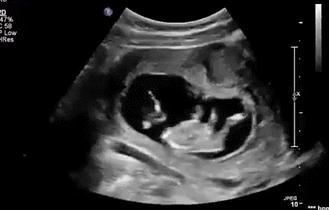

或者是这种

“肉浪滚滚”型